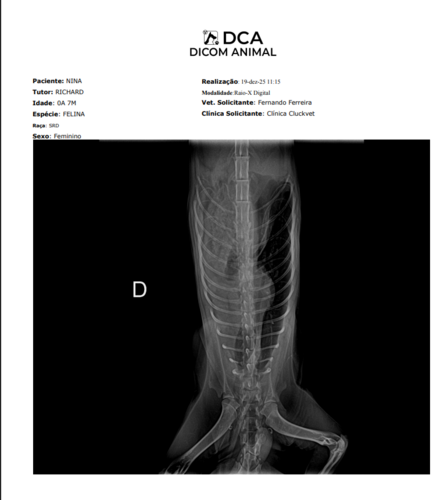

Meu nome é Richard, e Minha gatinha nina foi atropelada…, ela quebrou a perninha e rompeu o Diafragma dela, tive que fazer uma cirurgia de emergencia pois os orgãos dela tinham subido para o torax e estavam comprimindo o coração e pulmão dela, ela quase morreu. O preço da cirurgia foi de R$ 2300,00, e ainda falta a cirurgia da perninha dela que ainda segue quebrada. Todos esses custos são demais para mim bancar, e eu preciso de ajdua para fazer isso… A cirurgia de emergencia foi só para ajeitar o torax dela que estava bem delicado. Mas ainda preciso pagar e planejar a outra cirurgia dela, para a perninha dela, que ainda nem sei quanto vai custar…. Quem puder e quiser ajudar, por favor considere uma doação, qualquer quantia vai me ajudar e muito. Deixarei as imagens do raio X abaixo. E tentarei manter tudo atualizado para acompanharem o progresso.